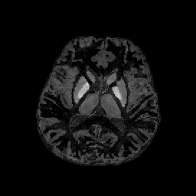

The in vivo MR data experiments are conducted using 256×256×146256256146256\times 256\times 146 image with spatial resolution 0.9375×0.9375×1mm30.93750.93751msuperscriptm30.9375\times 0.9375\times 1\mathrm{mm}^{3} which can be downloaded on Cornell MRI Research Lab webpage. Using the wrapped phase image presented in Figs. 12c and 13c, we unwrap the phase using the method in [21] to obtain the total field b𝑏b in Figs. 12d and 13d Then the measured local field data blsubscript𝑏𝑙b_{l} in Figs. 12e and 13e is obtained by solving the Poisson’s equation Eq. 2.12 using the method in [57].

Figure 12: Sagittal slice images of data sets for the in vivo MR data experiments.

Refer to caption